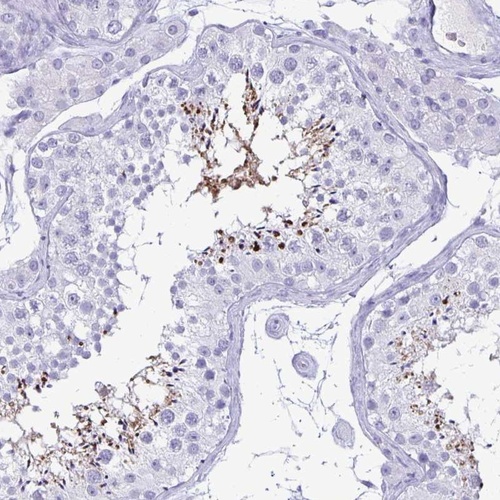

Immunohistochemistry analysis in human testis and endometrium tissues using Anti-BPIFA3 antibody. Corresponding BPIFA3 RNA-seq data are presented for the same tissues.